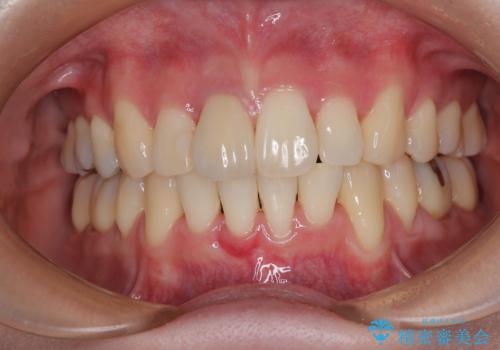

- 八重歯と上の前歯が出っ歯になっていることを気にして来院された患者様です。

横から見た際の口元の飛び出した印象も改善したいとのことで、上下左右の第一小臼歯4本を抜歯し、ワイヤー装置にて抜歯矯正を行うこととしました。

前歯の変色している歯は、神経組織が壊死していたため、矯正治療前に根管治療を実施し、矯正治療後にオールセラミッククラウンにて補綴治療を行うこととしました。

順調に歯が動き、補綴治療も含め2年弱で治療を終えることができました。